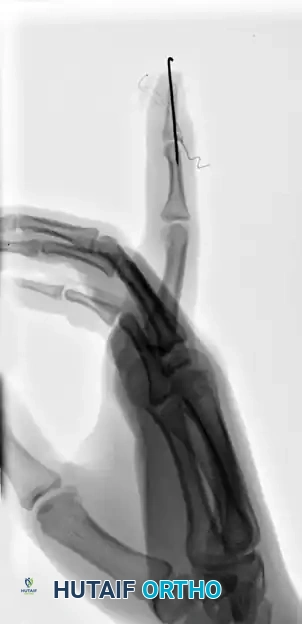

FIGURE 67-66 B: Radiographic results of the pull-out wire and transarticular pin fixation of the distal interphalangeal joint, demonstrating anatomic restoration of the articular surface. Images taken just before pin removal at 4 weeks.

FIGURE 67-66 C: The pull-out wire is typically left in place until 6 weeks after surgery to ensure complete bony union before dynamic stress is applied.